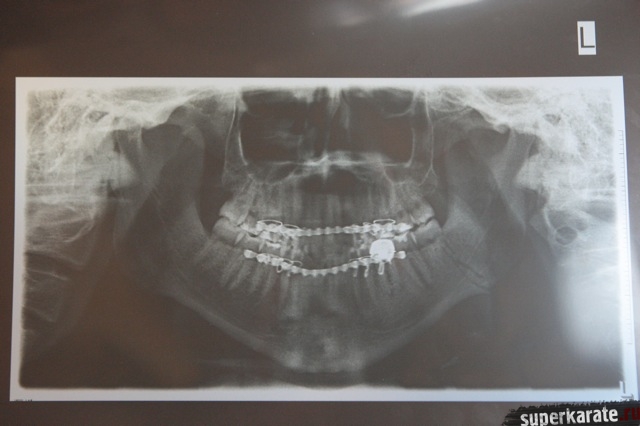

Обследование, проведенное в одной из лучших клиник города Афины квалифицированными греческими специалистами, прошло при участии официальных представителей Майка Замбидиса, мировой версии W5 и Московского общества греков. В рамках обследования Майку Замбидису был сделан рентгеновский снимок черепа, после чего снимок был подвергнут тщательному изучению. Также была проведен визуальный осмотр полученной травмы.

В результате полученных данных был сделан однозначный вывод о том, что Майк Замбидис действительно получил перелом нижней челюсти с левой стороны, и что дальнейшее продолжение боя могло привести к серьезным последствиям для здоровья Замбидиса.